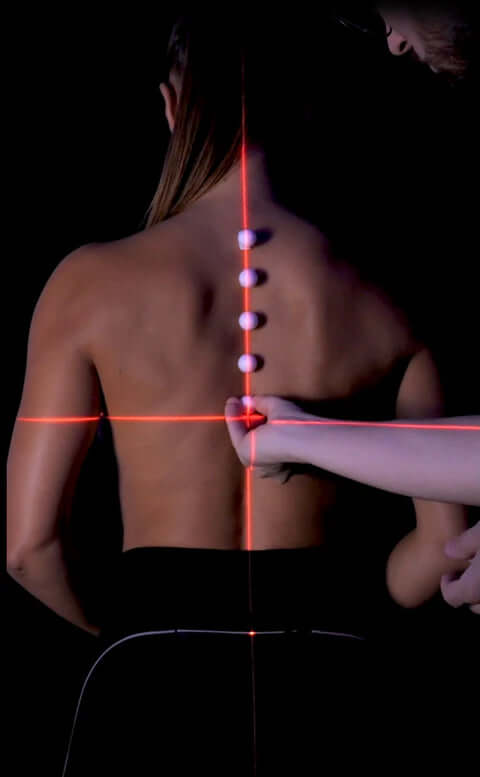

Allineamento vertebrale

Attraverso strumenti all'avanguardia ci impegniamo a monitorare il corretto allineamento del rachide cervicale in ogni posizione di riposo. Lo scopo è di assicurarci che non si verifichino condizioni che possano portare ad uno scompenso muscolare o scheletrico.